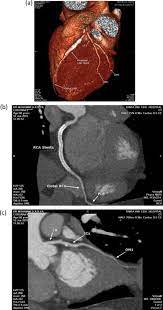

Infections Of Intravascular Bare Metal Stents A Case Report And Review Of Literature European Journal Of Vascular And Endovascular Surgery

Infections Of Intravascular Bare Metal Stents A Case Report And Review Of Literature European Journal Of Vascular And Endovascular Surgery from els-jbs-prod-cdn.jbs.elsevierhealth.com